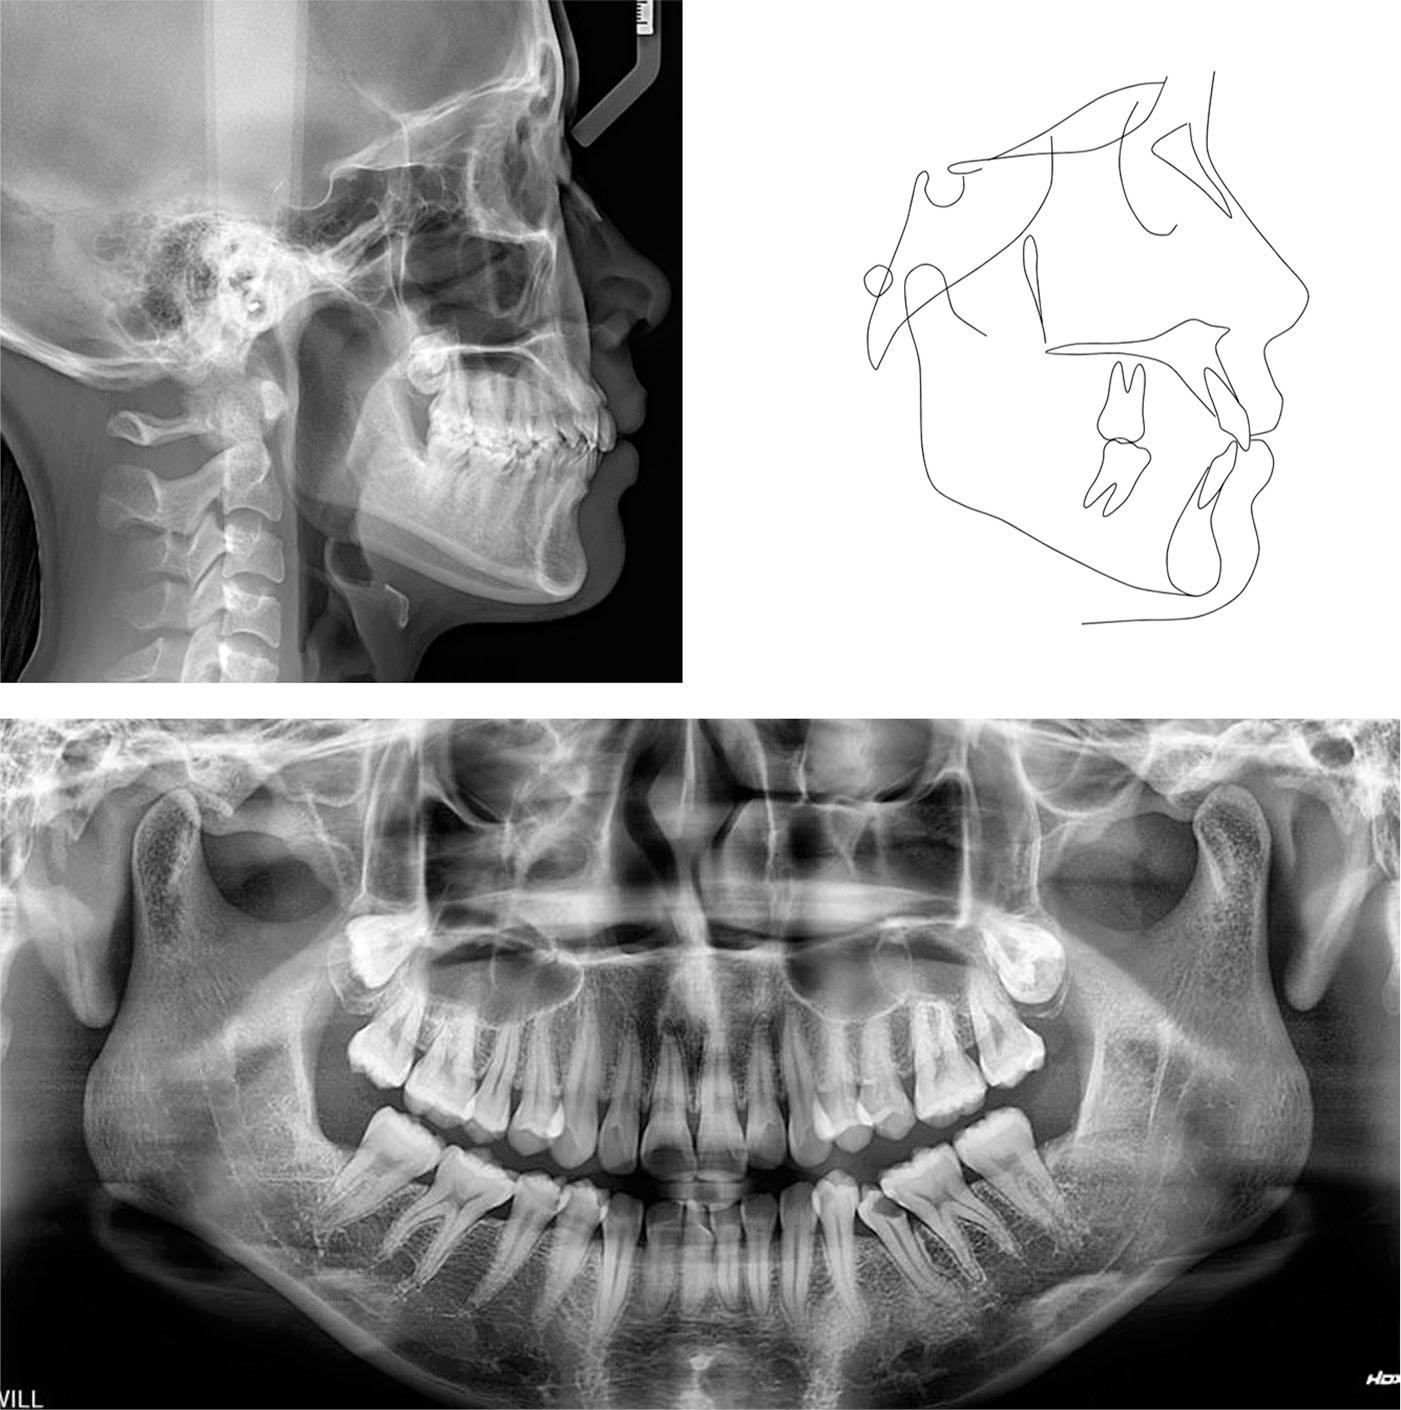

Figure 1.